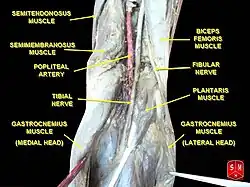

| Normal course of the popliteal artery at the back of the knee | |